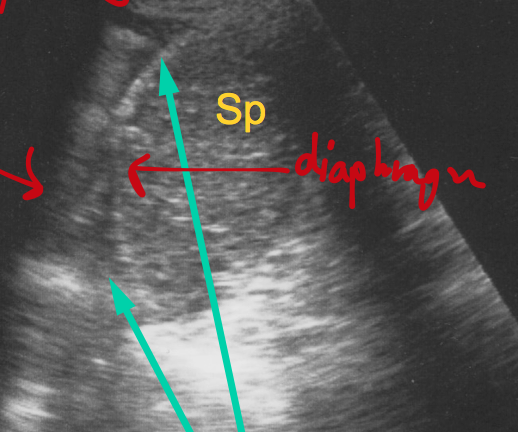

Where is this.

Label it/

RUQ